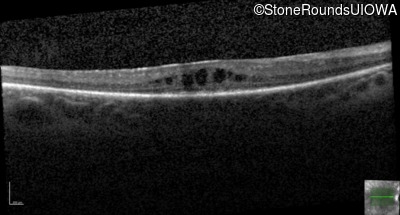

Optical Coherence Tomography - Left - 20/70 +1

Exemplar / OCT Stack